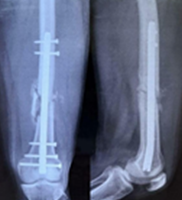

A few cases are illustrated in the Figs. 1, 2, 3, 4.

Figure 4: A 32 year male patient with crush injury following road traffic accidents involving multiple digits (a and b), X-ray – fracture middle phalanx of index finger (IF) and shaft of 5th metacarpal (MC) (c), Treatment: Wound debridement + open reduction internal fixation and K-wire fixation of IF + Miniplate screw fixation of 5th MC + local flap (cross finger flap cover) over raw area (IF) (d), Follow-up (1 month): K wire in situ + division of cross finger flap with follow-up (e-g).